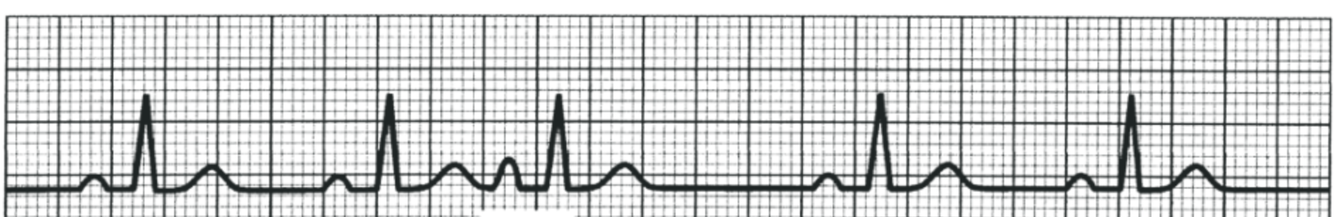

What is this?

2nd Degree AV Block - Mobitz Type I (Wenckebach)

PR interval progressively lengthens until QRS is dropped